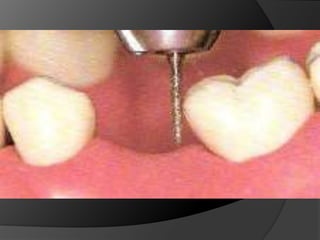

Preparaciones dentales en prótesis fija

EXISTEN TRES ASPECTOS DE PREPARACIÓN DENTAL FUNDAMENTALES EN EL ÉXITO DE LA  RESTAURACIÓN DEFINITIVA O FINALReducción OclusalReducción AxialReducción Interproximal

Reducción InterproximalTodas las paredes del diente deben ser reducidas para asegurar el espesor adecuado del materialPor la anatomía dental, donde el punto de contacto  es en la zona más ancha, el desgaste proximal es más extenso.Especial cuidado con el diente contiguo durante la prepraración

Al preparar dientes se debe tener altísima precaución con la velocidad y torque de las piezas de alta y con la refrigeración  utilizada.El sobrecalentamiento puede producir inflamación pulparllegando hasta necrosis.En dientes desvitalizados, el tallado en seco debe evitarse, pues el estrés térmico causarámicrofracturasen esmalte